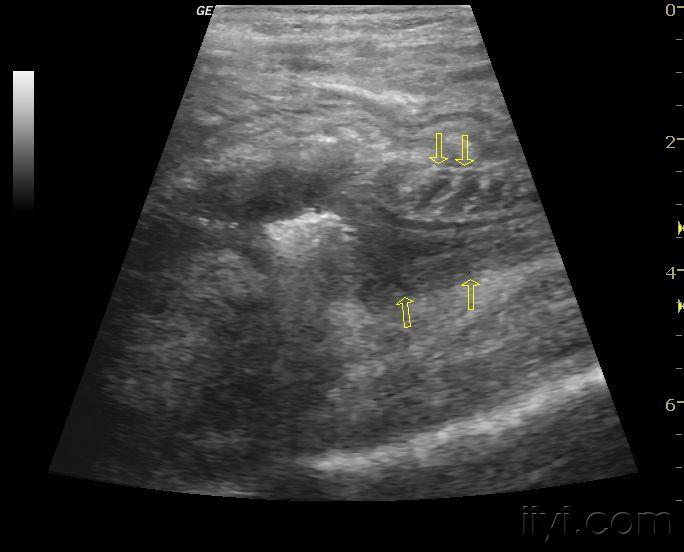

发几张自己做的小儿肠套叠的图,比较典型 - 超声医学讨论版 - 爱爱医

图片尺寸768x576